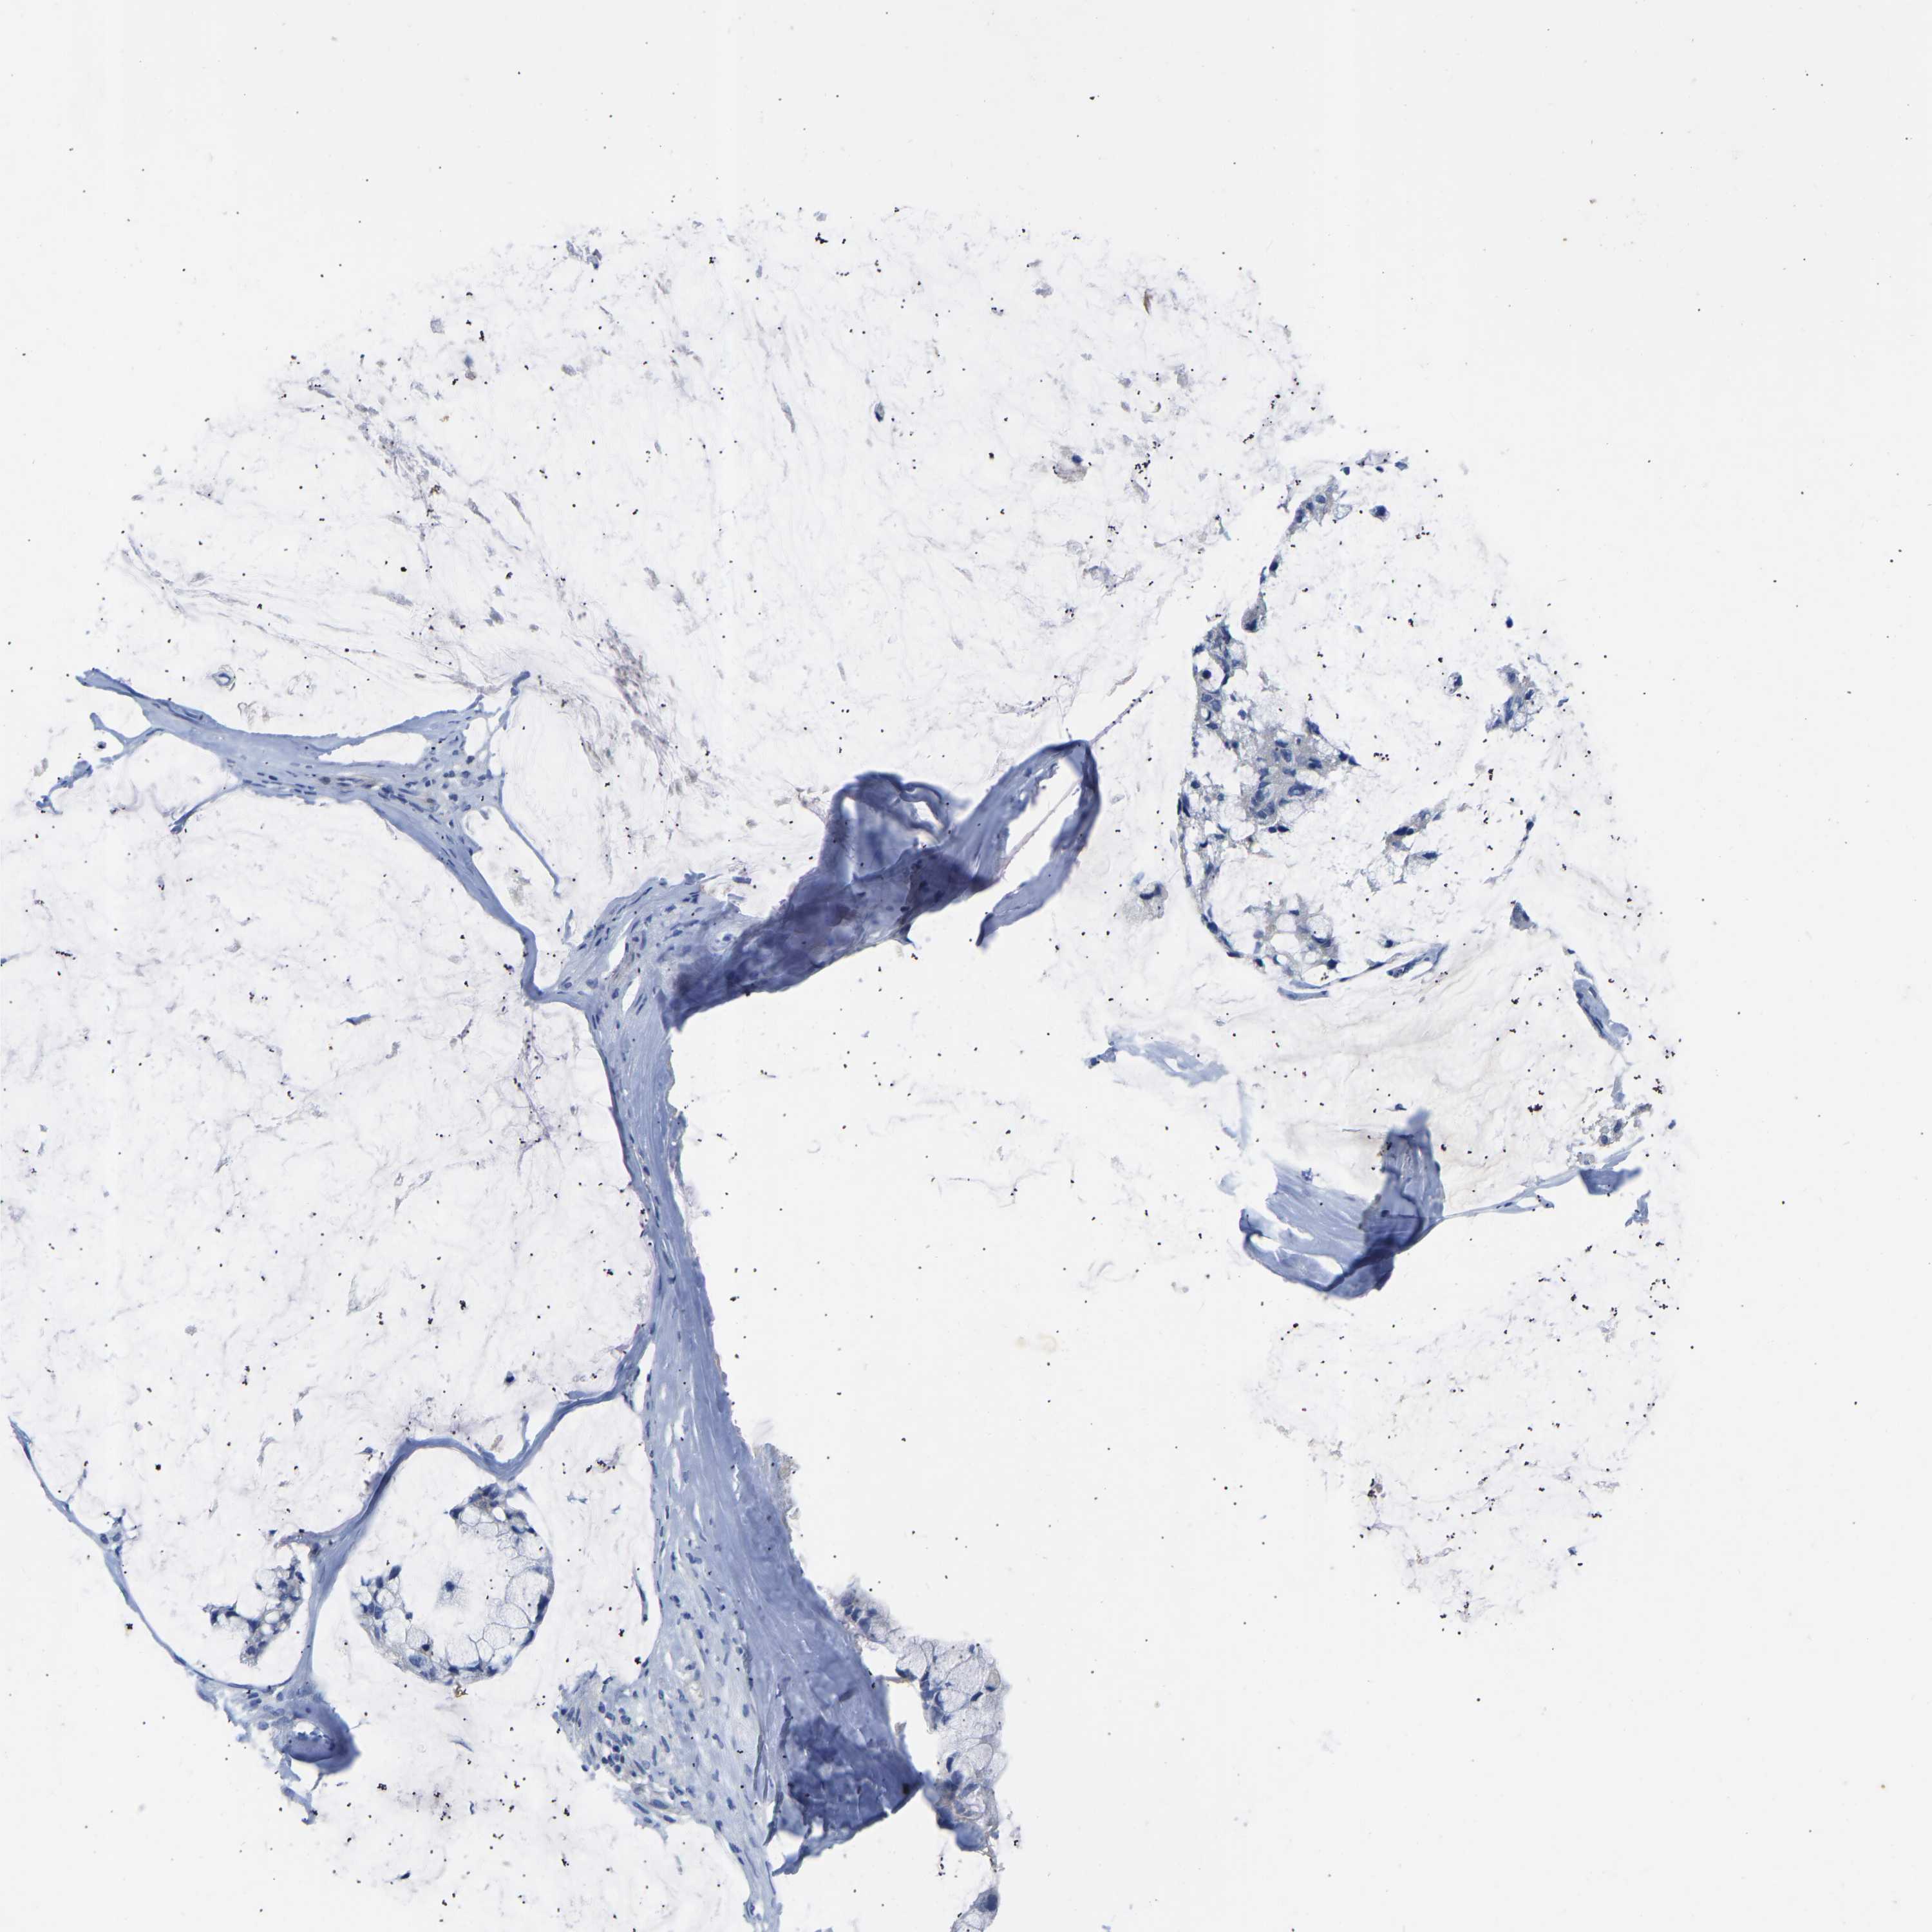

OVARIAN CANCER - Protein expressioni

A mouse-over function shows sample information and annotation data. Click on an image to view it in a full screen mode. Samples can be filtered based on level of antibody staining by selecting one or several of the following categories: high, medium, low and not detected. The assay and annotation is described here.

Note that samples used for immunohistochemistry by the Human Protein Atlas do not correspond to samples in the TCGA dataset.

Antibody stainingi

Antibody staining in the annotated cell types in the current human tissue is reported as not detected, low, medium, or high, based on conventional immunohistochemistry profiling in selected tissues. This score is based on the combination of the staining intensity and fraction of stained cells.

Each image is clickable and will lead to virtual microscopy that enables deeper exploration of all samples and also displays staining intensity scores, fraction scores and subcellular localization as well as patient and tissue information for each sample.

Antibody HPA007338

Antibody CAB018603

Antibody CAB019276

Staining

High

Medium

Low

Not detected

Cystadenocarcinoma, serous, NOS

Cystadenocarcinoma, mucinous, NOS

Carcinoma, endometroid

Carcinoma, NOS